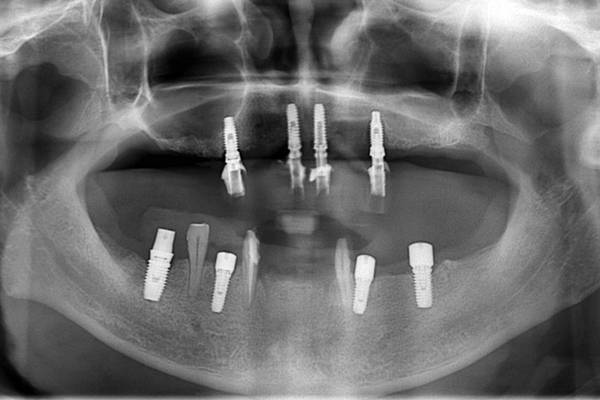

그림 2. 상악에 4개의 임플란트를 식립하여 고정성 PFM 수복물을 계획한 경우입니다. 여기서 2개의 임플란트는 급여, 나머지 2개의 임플란트는 비급여로 적용할 수 있을까요? 처음 임플란트를 식립한 상태가 완전무치악이기 때문에 4개의 임플란트 모두가 비급여에 해당합니다. 만약 2개의 임플란트를 급여적용하기를 원한다면, 먼저 완전무치악의 우측이나 좌측에 2개의 임플란트를 비급여로 식립하고 PFM 보철물로 수복을 완성하여 완전무치악을 부분무치악 상태로 바꾸어야 합니다, 그리고 나서 나머지 2개의 임플란트를 식립하여야 부분무치악에 식립한 것이 되므로 급여로 적용할 수 있습니다. 만약 4개의 임플란트를 동시에 식립하고 2개의 임플란트를 급여청구하면 비급여에 해당하는 진료를 부당하게 급여청구한 것이 되기 때문에 허위청구에 해당하게 됩니다.